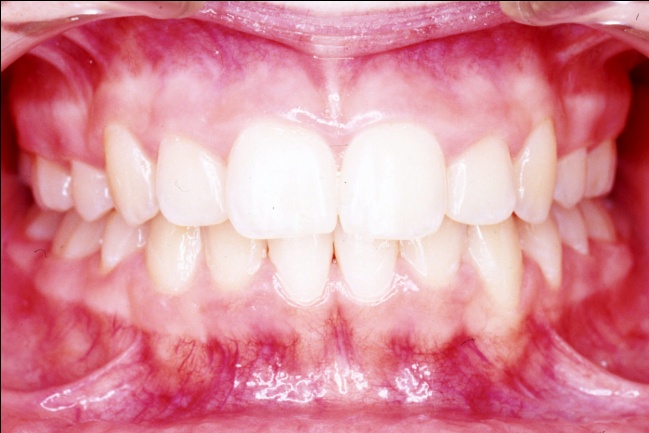

1 - Arcades dentaires avant-après traitement

Les photos montrent, avant traitement, des dents supérieures projetées vers l’avant et encombrées. Après traitement, les arcades, ayant subi l’extraction de prémolaires, présentent un articulé redevenu normal et un alignement complet. Ce résultat positif ne reflète pourtant pas toute l’ampleur des changements : en orthodontie, les dents soutiennent directement les lèvres, et toute modification de leur position influence le profil. Ici, le repositionnement dentaire a eu un effet déterminant sur l’harmonie des tissus mous.

2 - Quand l’orthodontie redessine le visage

Avant traitement, le sourire de profil montre des dents projetées hors de la cavité buccale, avec une incompétence labiale marquée et un profil cutané présentant une biprochélie importante associée à un angle nasolabial très fermé. Après traitement, la transformation est spectaculaire : les dents sont repositionnées dans la bouche, les lèvres se ferment naturellement au repos, le profil est harmonisé, moins protrusif, et l’angle nasolabial a retrouvé une ouverture normale.